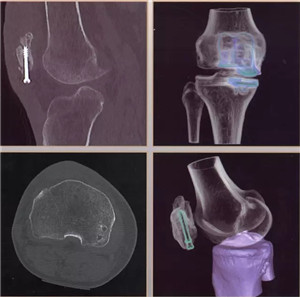

图像分辨超清:0.23毫米的空间分辨率,对于2毫米冠脉支架的细节和支架内再狭窄清晰可辨;可超早期发现微小肿瘤病变。

辐射剂量超低:超低的辐射剂量,带来更高清的图像,疾病筛查、儿科、肾功能不全患者也可放心使用。